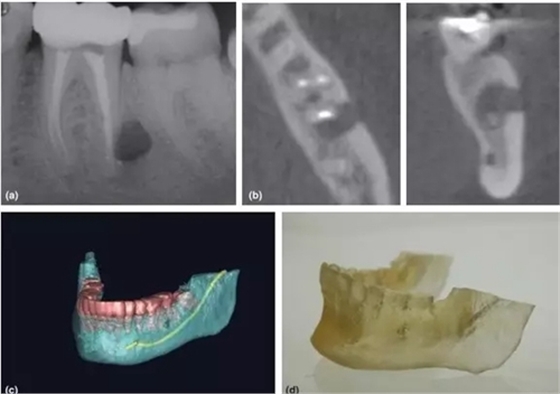

3,根尖周手術(shù)的術(shù)前評估

CBCT一直被倡導(dǎo)用于評估和設(shè)計(jì)根尖周手術(shù)方案 (Rigolone et al. 2003; Tsurumachi & Honda 2007; Kim & Kratchman 2006)。三維重建圖像讓臨床醫(yī)生能判斷根尖與鄰近重要解剖結(jié)構(gòu)的關(guān)系,如下頜神經(jīng)管、髁孔和上頜竇等。除外,還能精準(zhǔn)測量骨損實(shí)際大小、與牙根的關(guān)系、皮質(zhì)骨板厚度、骨開窗情況和牙根的傾斜角度(Nakata et al. 2006)。

CBCT掃描還能配合3D打印技術(shù),把掃描的術(shù)區(qū)立體重建并打印出來,得出真實(shí)比例的研究模型,有助于術(shù)者對手術(shù)方案的設(shè)計(jì)和過程的演練(Scarfe et la. 2006)。

a-根尖片顯示31牙根吸收;b,c,d-對31的CBCT掃描清楚顯示內(nèi)吸收范圍和程度,舌側(cè)牙根已穿通;

對于牙根吸收的情況,CBCT能反映病損來源、位置和進(jìn)展程度,有助于治療方案的制定。例如外吸收一般只能通過手術(shù)進(jìn)行干預(yù),而內(nèi)吸收則需要根據(jù)程度來判斷保留價(jià)值。